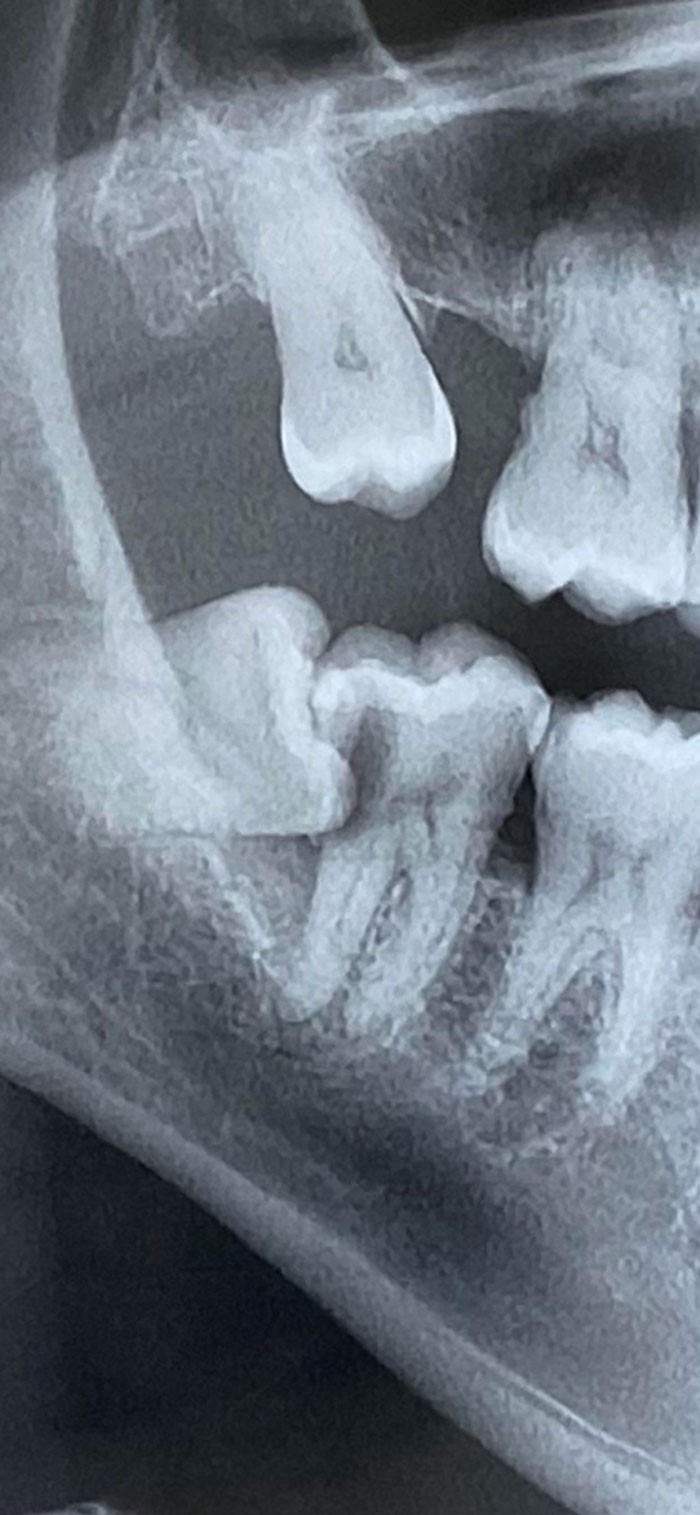

10. Последствия выстрела в локоть из дробовика 12-го калибра на рентгеновском снимке